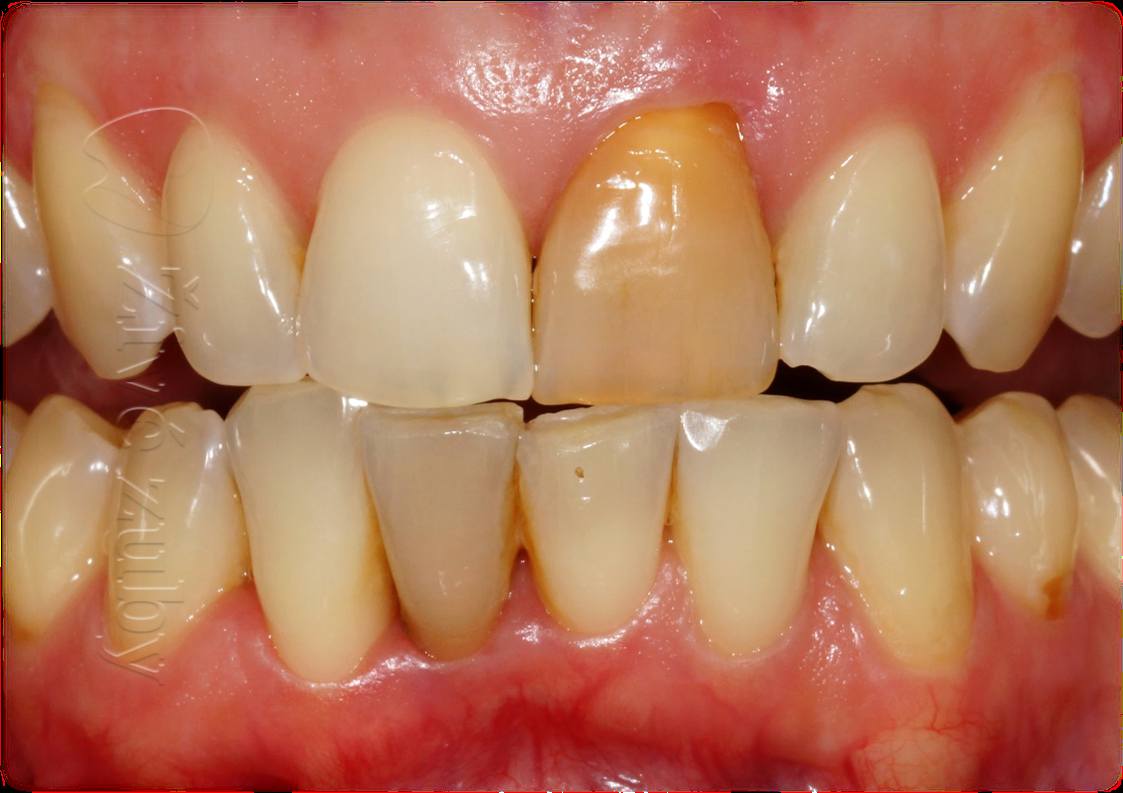

Vnitřní bělení zubů